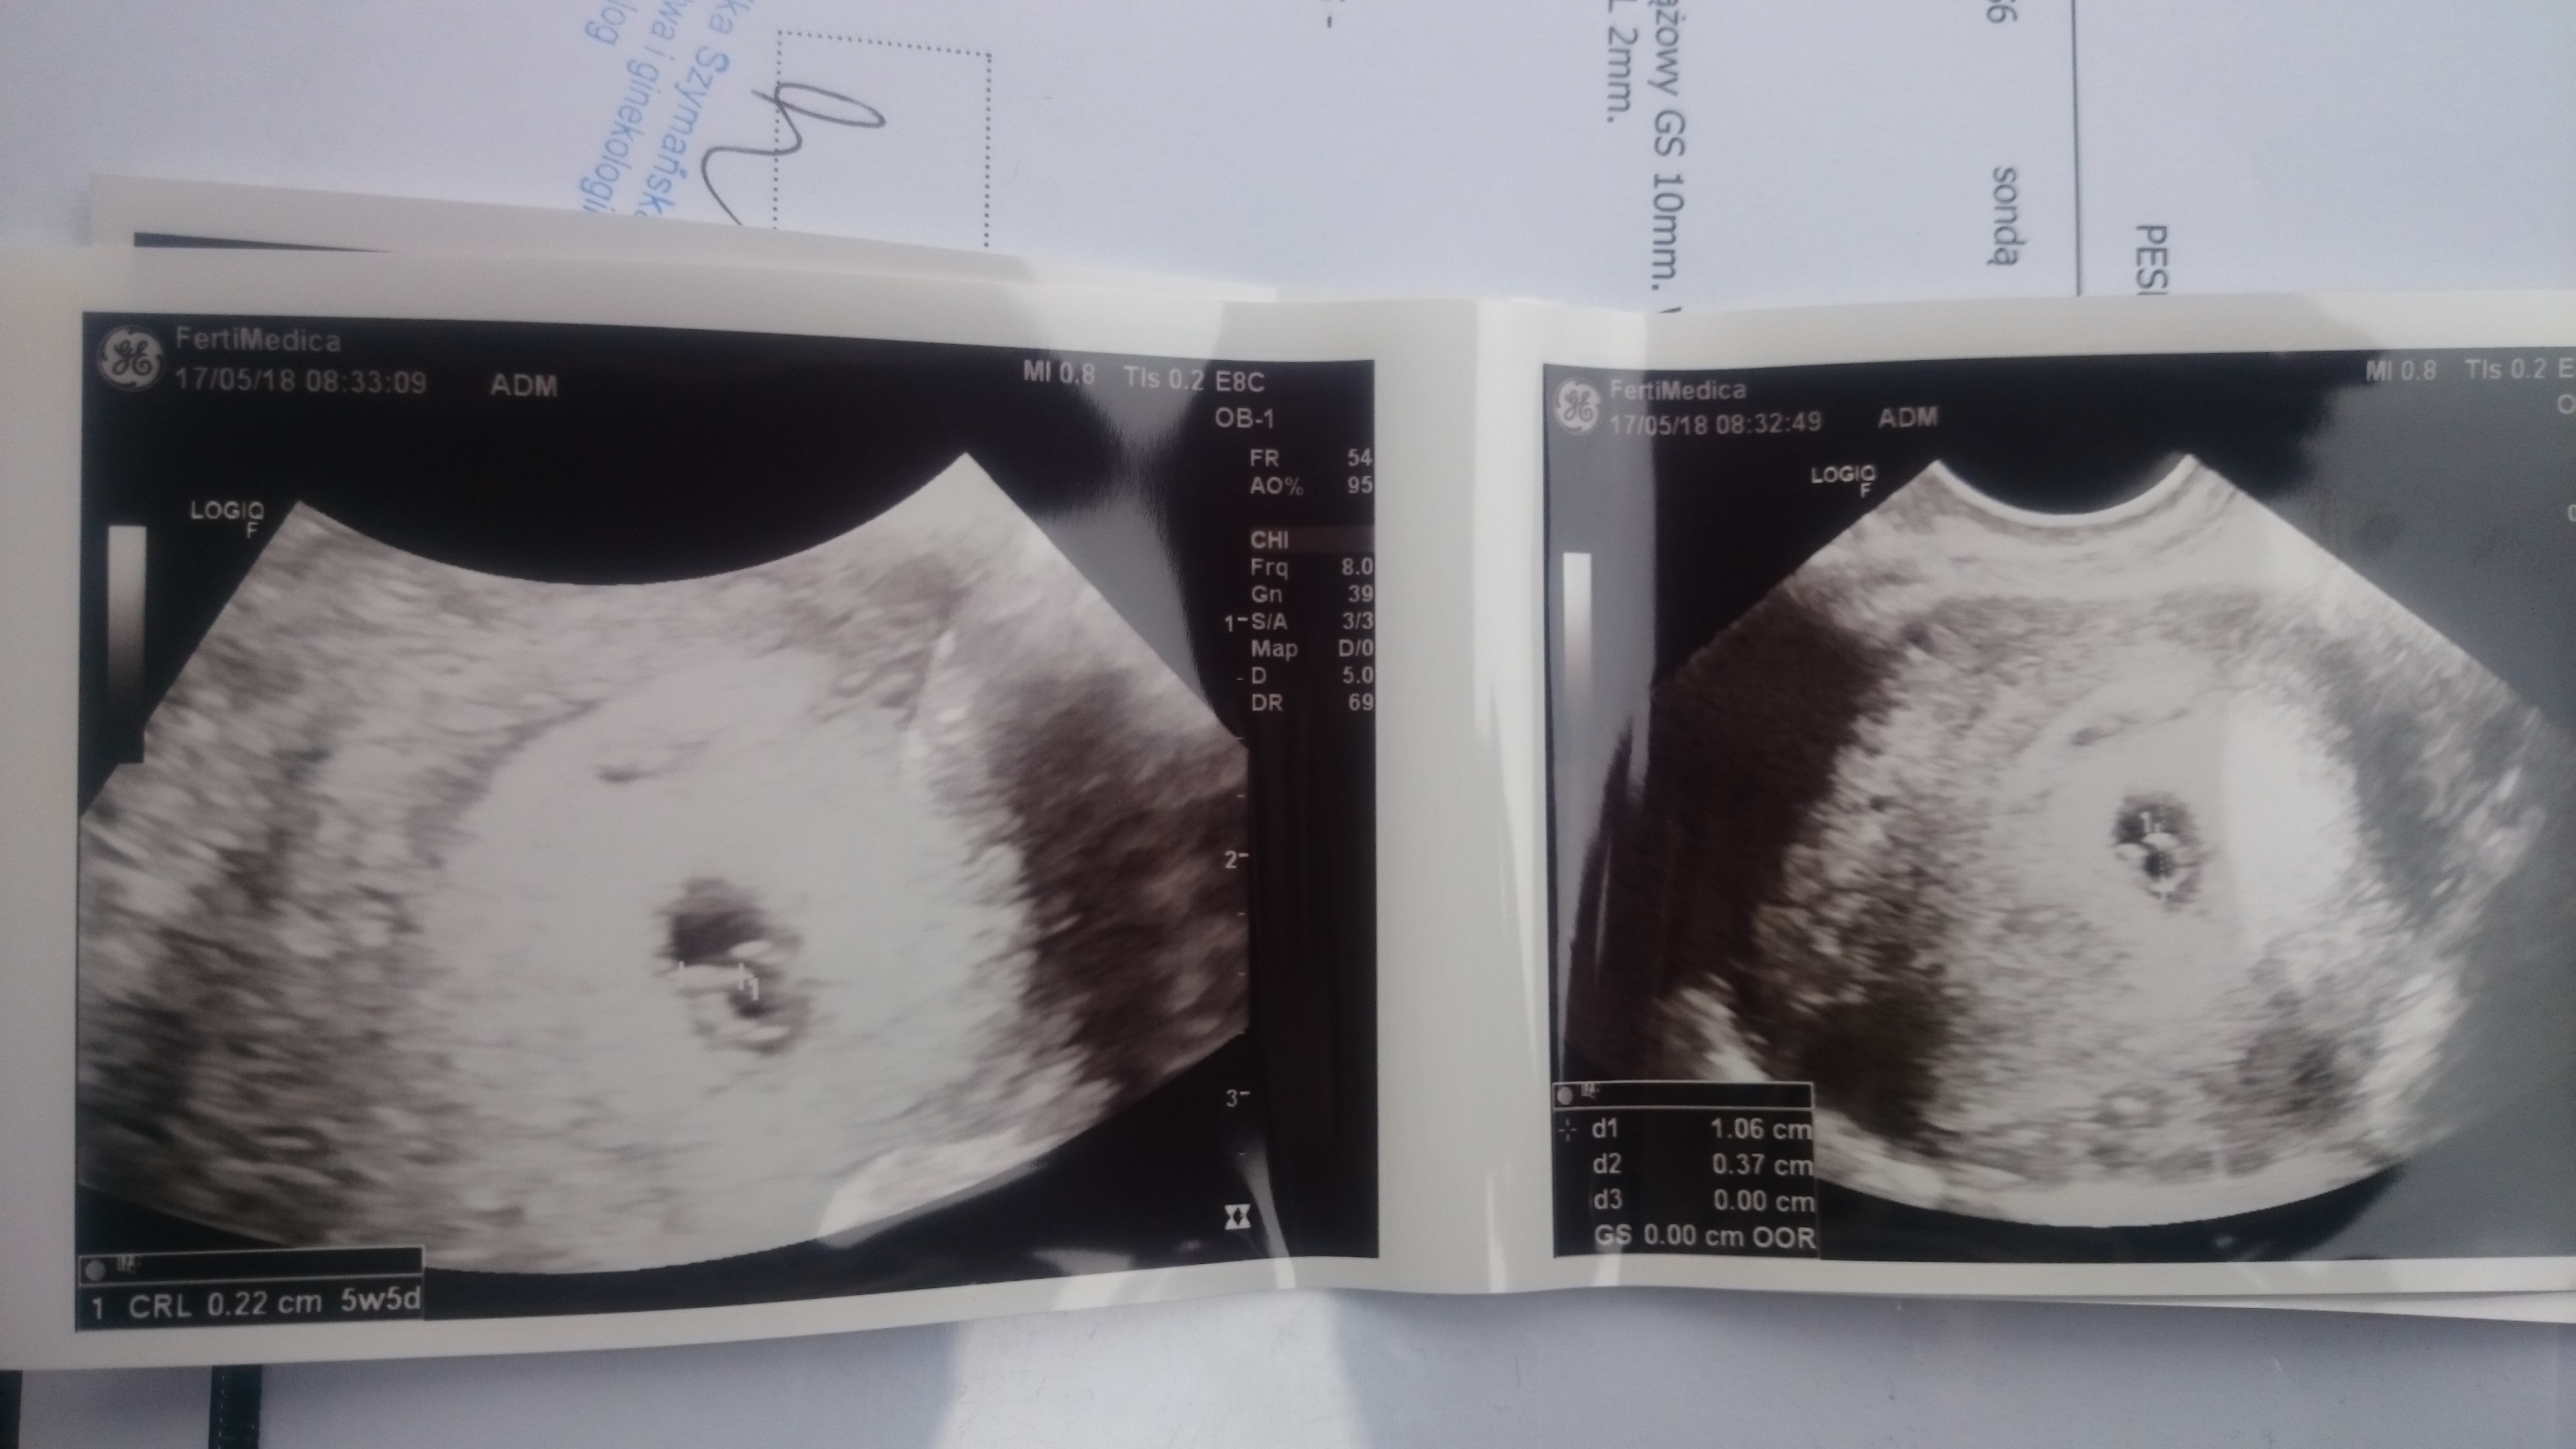

Dzien dobry [emoji4] jestem mega malusi, ale juz jestem. 5t5d. Tak jak wg om. Na tą chwilę jest wszystko w porządku. Dostałam 5mg kwasu bo Pani Doktor uważa, ze jeżeli coś nie szkodzi w nadmiarze, a może pomóc to lepiej łykać. Zobacz załącznik 860080

Reqiem, właśnie uświadomiłam sobie, że miałam usg też dokładnie w 5tyg i 5 dniu i mój Kropek miał identyczny wymiar jak Twój 2,2 mm :D Zobacz!

Jej to super, ze to mowisz bo jakos z tyłu głowy myslalam, ze jest troche za mały bo Doktor cos miwila, zanim zobaczyła kropka, ze pecherzyk ciazowy troszke mały bo 8.6mm i utkwiło mi to we łbie [emoji14][emoji14]

U mnie co prawda na tamtym etapie pęcherzyk ciążowy 10 mm, ale spokojnie :) fasolka go rozepcha do większych rozmiarów ;)